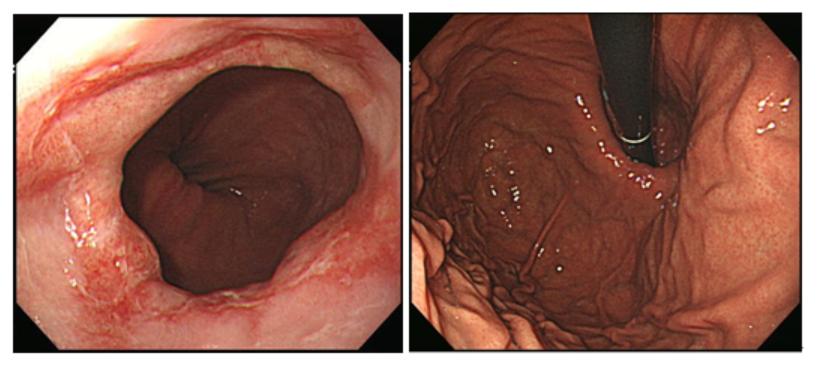

식도열공탈장을 동반한 심한 미란성 역류성 식도염 에서의 처방 사례 < CME < 기획·특집 < 기사본문 - 청년의사